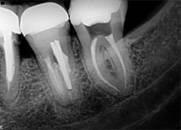

antes depois